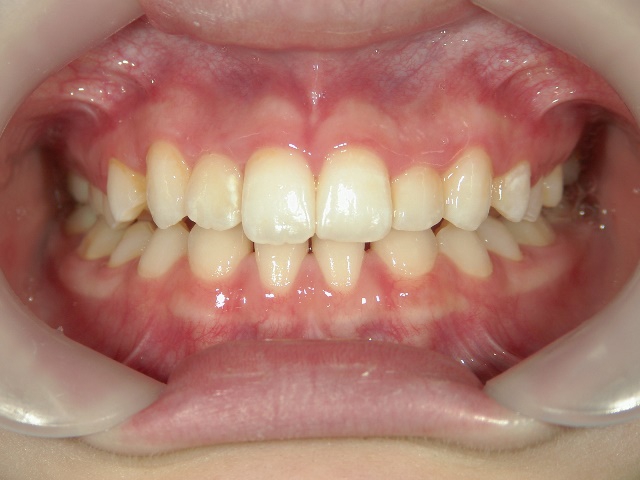

矯正歯科 治療前 正面